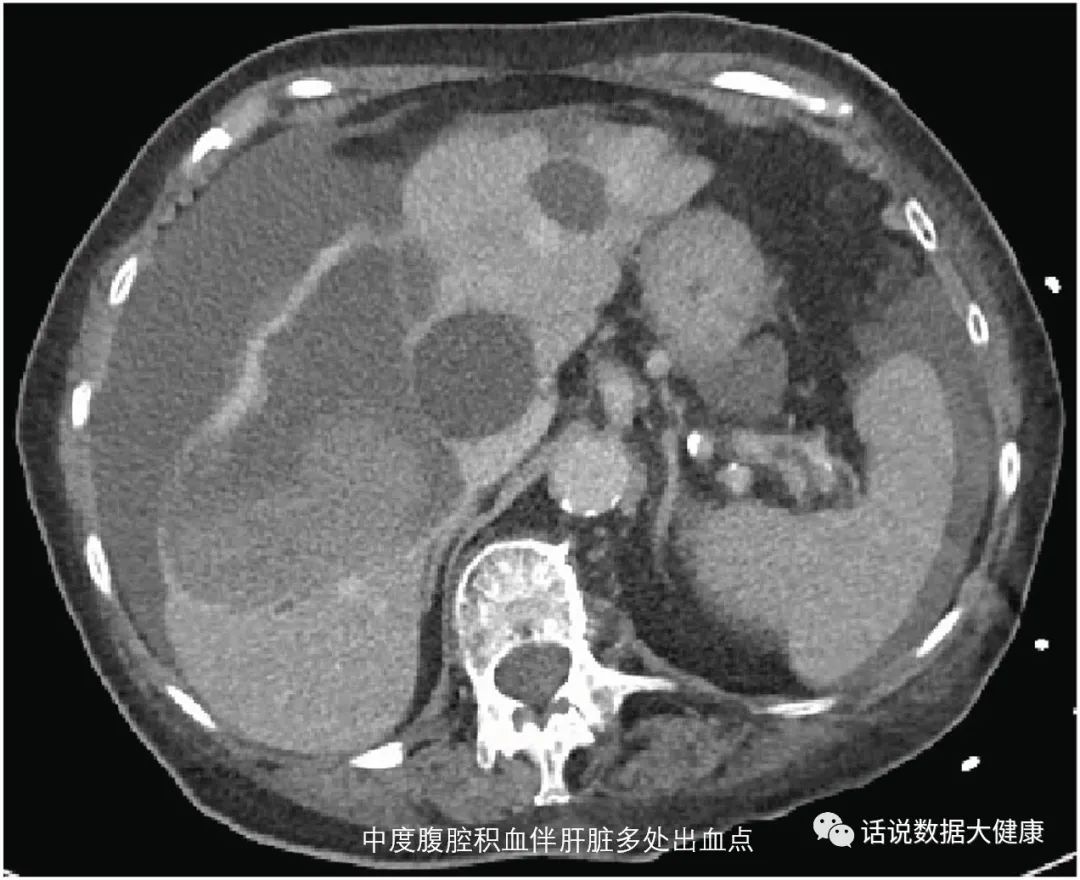

服用纳豆安全吗?目前美国食品和药物管理局认为服用纳豆(纳豆激酶)产品并不是普遍安全的。加拿大卫生部认定纳豆激酶有增加出血的潜在风险。某女性,52岁,患有高血压,1年前查体时发现有腔隙性脑梗塞,每天服用降压药和100mg阿司匹林,听闻纳豆保健品中宣传内容后,1周前开始 服用纳豆激酶400mg/天预防脑卒中 ,出现了眩晕和站立不稳,经检查出现急性小脑出血和多发散在出血灶。

临床报道某女性,既往有阵发性房颤,未服用任何抗凝药, 每天服用纳豆激酶( 具体量不详)。因摔倒门诊查体发现腹腔内出血,入院后给与止血、输血等治疗,后因严重低血压去世。